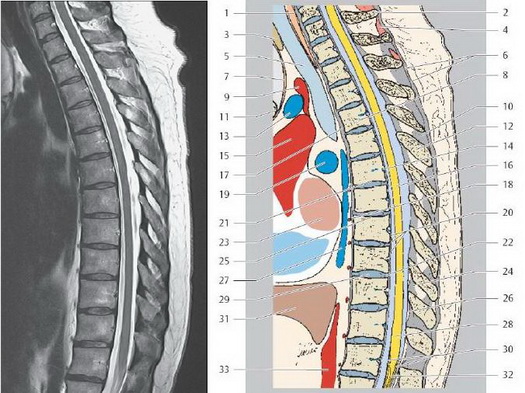

Грудной отдел позвоночника

1. Пищевод

2. Седьмой шейный позвонок

3. Щитовидная железа

4. Межостистая мышца шеи

5. Трахея

6. Надостистая связка

7. Грудиноподьязычная мышца

8. Тело грудного позвонка Т4

9. Плечеголовной ствол

10. Межостистая связка

11. Грудина (рукоятка)

12. Остистый отросток

13. Левая плечеголовная вена

14. Базально-позвоночная вена

15. Восходящая аорта

16. Грудной отдел спинного мозга

17. Передняя продольная связка

18. Задняя межреберная артерия

19. Легочная артерия

20. Задняя продольная связка

21. Нижняя концевая пластинка позвонка Т6

22. Межпозвоночный диск Т9/Т10

23. Левое предсердие

24. Желтая связка

25. Верхняя концевая пластинка позвонка Т7

26. Эпидуральная жировая клетчатка

27. Непарная вена

28. Мозговой конус

29. Межпозвоночный диск Т9/Т10

30. Конский хвост

31. Печень

32. Концевая нить спинного мозга

33. Нисходящая аорта